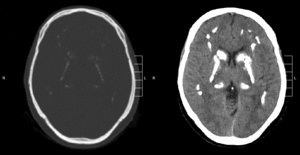

Primary familial brain calcification[1] (PFBC), also known as familial idiopathic basal ganglia calcification (FIBGC) and Fahr's disease,[1] is a rare,[2] genetically dominant, inherited neurological disorder characterized by abnormal deposits of calcium in areas of the brain that control movement. Through the use of CT scans, calcifications are seen primarily in the basal ganglia and in other areas such as the cerebral cortex.[3]

| CT scan of characteristic calcifications of the disease | |

Brain CT scan is the preferred method of localizing and assessing the extent of cerebral calcifications.

The calcification is usually identified on CT scan but may be visible on plain films of the skull.